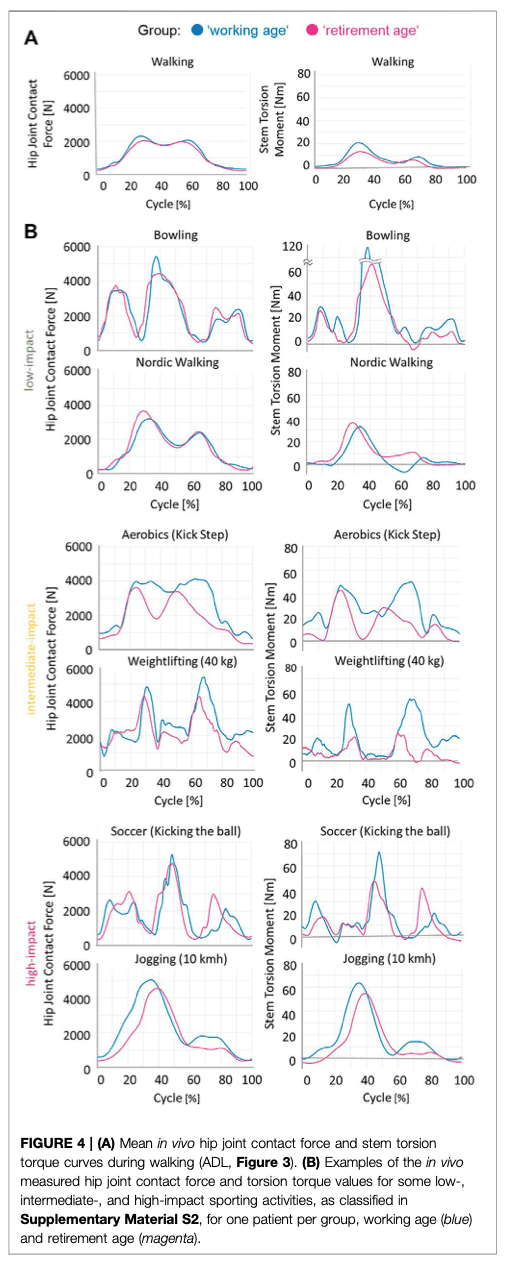

Има какво да се каже за тази обобщаваща таблица. Bender, 2022 г. измерва in vivo сили на контакт със ставите и усукващи моменти и установява, че боулингът, който се счита за дейност с ниско въздействие, например, предизвиква по-високи сили на контакт със ставите и усукващи моменти в сравнение с футбола с високо въздействие. Освен това те установяват, че телесното тегло и индексът на телесна маса оказват влияние върху тези сили по време на ежедневни дейности.